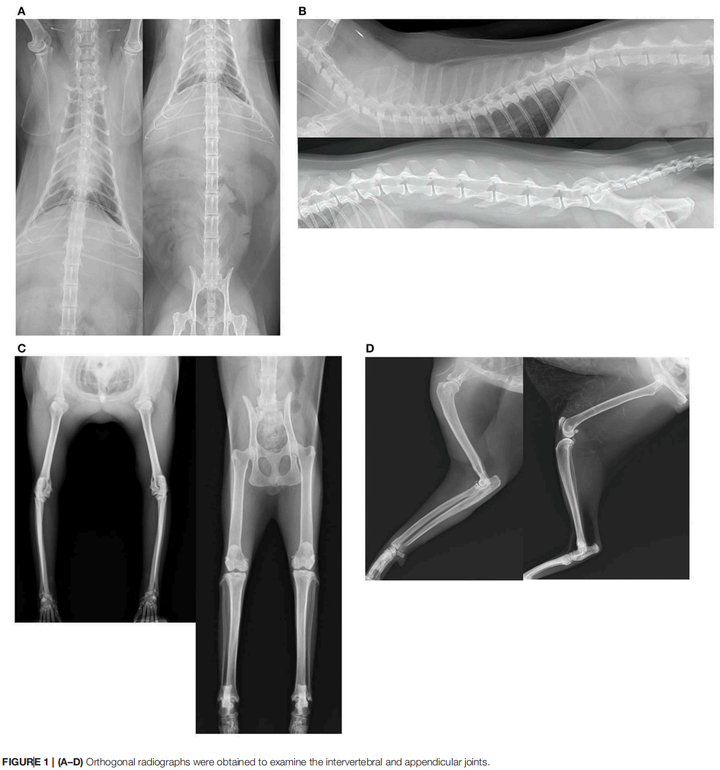

一只猫的关节已经在 X 光片上布满了退行性病变的痕迹,走路的时候每一步都在承受骨头磨骨头的摩擦,但它的主人什么都没察觉。

2020 年,一个日本研究团队给 101 只猫做了全面的骨骼 X 光筛查,其中 75 只存在四肢关节退行性病变,41 只存在脊椎退行性病变。

四肢关节有问题的 75 只猫里,主人注意到跛行的只有 1 位;脊椎有问题的 41 只里,主人注意到步态异常的也只有 1 位。整个研究中,兽医触诊时没有任何一只猫表现出明显的关节疼痛[1]